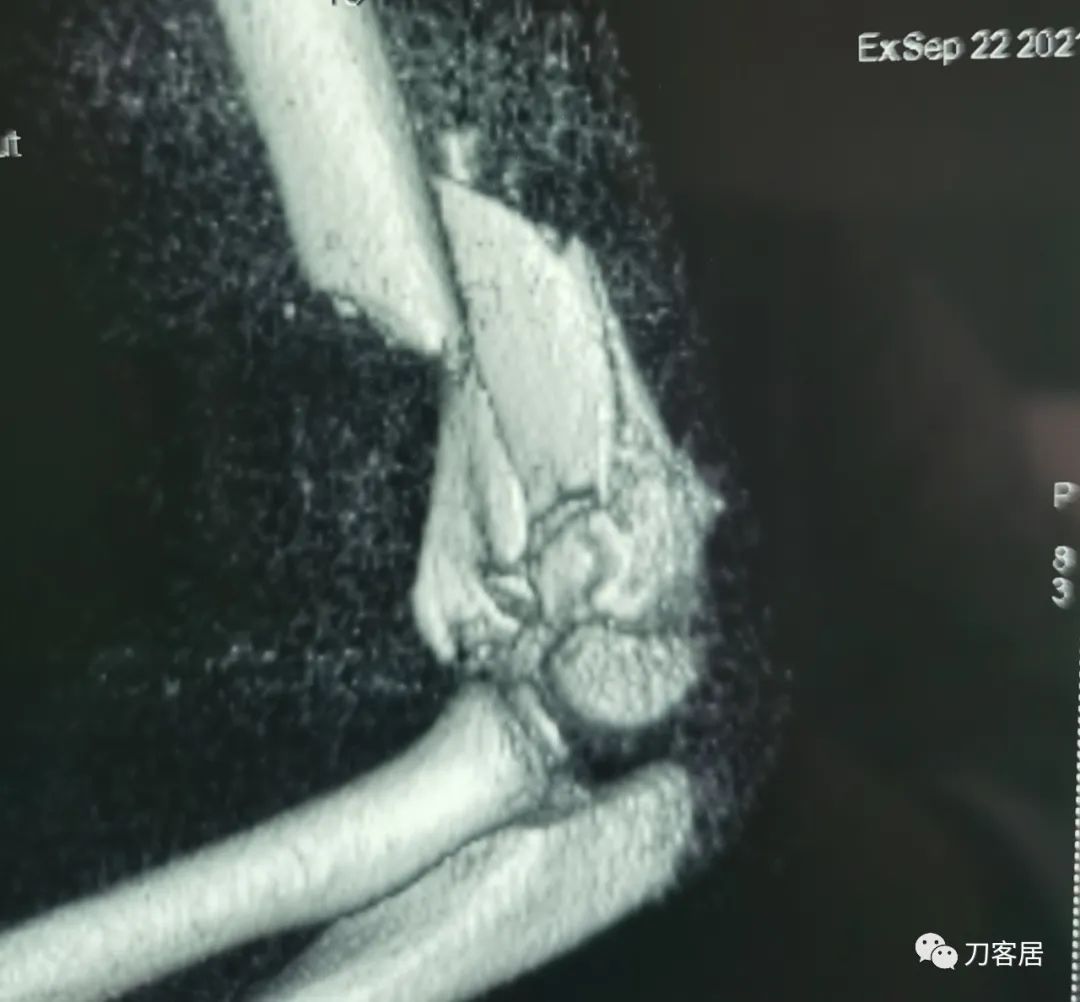

查体:左侧肘关节肿胀明显、疼痛、畸形,局部可见明显青紫瘀斑,左肘关节活动受限,肱骨远端环形压痛(+),局部可及异常活动及骨擦感形成,左上肢末梢桡动脉可触及,左侧腕关节及拇指背伸活动受限,左侧虎口区感觉麻木。辅助检查:自带X线及CT片示:左肱骨髁间粉碎性骨折。

入院诊断:1. 左肱骨髁间粉碎性骨折;2.左肱骨远端骨骺损伤;3. 左桡神经损伤。

20210922当地省中医院三维CT01

20210922当地省中医院三维CT09